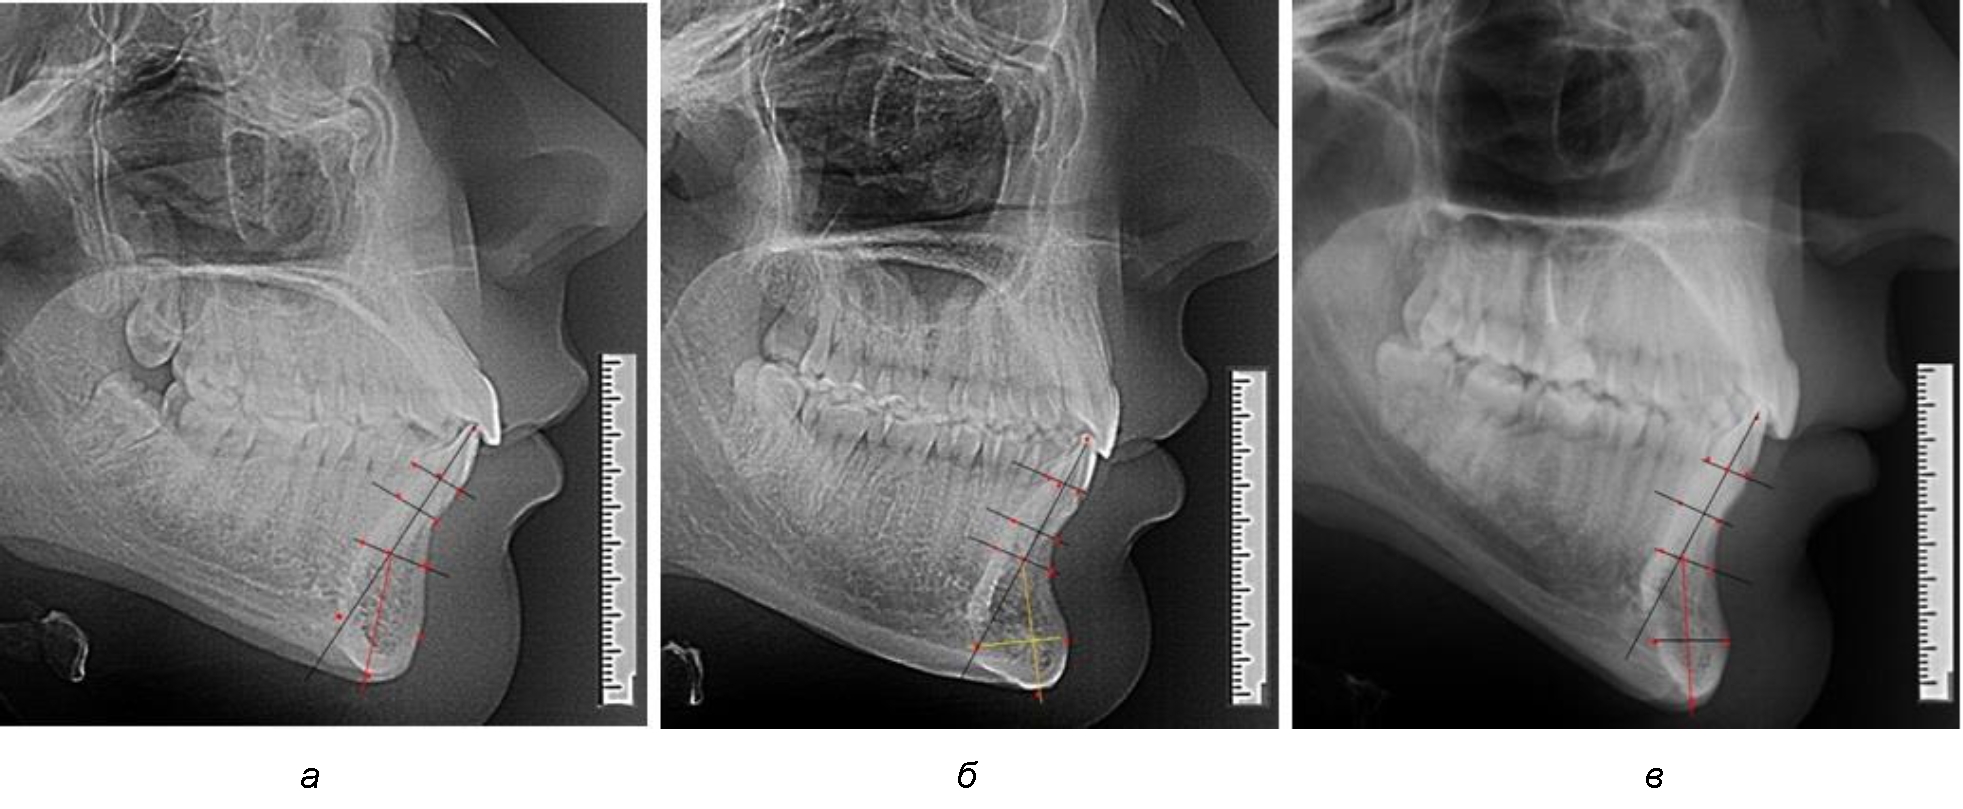

Рис. 1. Ориентиры для исследования нативных препаратов (а) и рентгенограмм (б) резцового нижнечелюстного сегмента

Рис. 3. Варианты среднего (а), широкого (б) и узкого (в) нижнечелюстного резцового сегмента

Варианты резцовых сегментов нижней челюсти различные как по ширине, так и по высоте, а также по расхождению положения апикальных точек по Downs и Schwarz представлены на рис. 4.

Рис. 4. Особенности нижнечелюстного резцового сегмента на ТРГ у людей при среднем (а), широком (б) и узком (в) вариантах